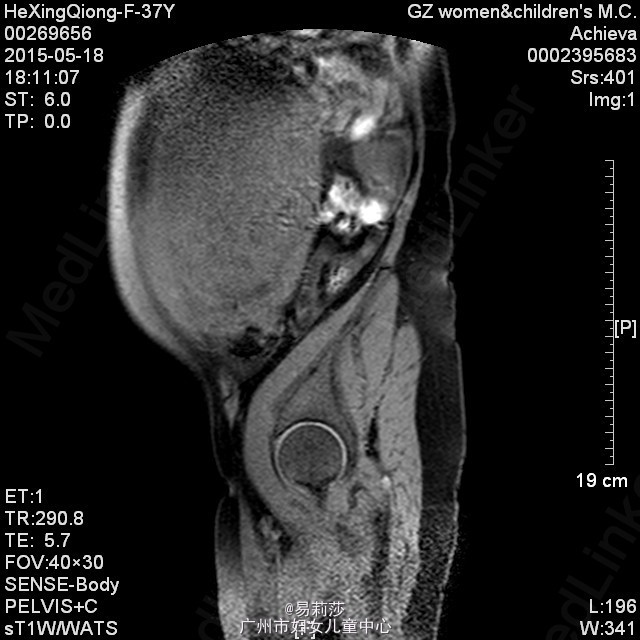

患者何××,女,G0P0,36岁,因“体检发现子宫肌瘤半年”于2015-06-23入院。患者平素月经规则,LMP:2015-06-12。患者于半年前体检时发现子宫肌瘤,未治疗。2月前,患者自觉腹部包块逐渐增大,2015-05-12彩超检查示:子宫前位,后壁见一实性低回声团,范围约125×193×192mm,边界尚清,明显外突,内回声欠均匀,宫腔线隐约可见,双侧附件因肿块遮挡,显示不清,CDFI:上述低回声团内见短棒及条索状血流信号,查血常规示:血红蛋白31g/L,拟“子宫平滑肌瘤”收入我科。入院后查贫血组合示缺铁,予输红细胞悬液6个单位,复查血色素81g/L,患者要求出院,此次再次入院要求手术治疗。查体:T36.2℃,P100次/分,R20次/分,BP132/74mmHg,神清,中度贫血外观,心肺听诊无异常,腹膨隆,宫底达剑突下1cm,无压痛、反跳痛。妇科检查:外阴发育正常,阴毛女性分布;阴道畅,分泌物色白,无异味;宫颈光滑,无肥大,无举痛及着色;宫体前位,增大,宫底达剑突下1cm,质硬,活动差,无压痛;双侧附件未扪及包块及压痛。 辅助检查:2015-06-24彩超检查示:胆囊息肉(胆固醇结晶),副脾,肝、胰、右肾未见明显异常回声,左肾下极异常回声团——畸胎瘤?,考虑来源左侧卵巢可能,与左肾关系密切,巨大子宫肌瘤,左侧卵巢显示不清,请进一步检查。MRI检查示:1.子宫左侧壁巨大实性肿块影,考虑巨大子宫肌瘤可能性大,子宫明显受压;2、左肾下方类圆形病变,考虑畸胎瘤可能性大;3、双侧腹膜后区主动脉、下腔动脉周围见不规则囊状影,考虑淋巴管扩张可能;4、盆腔少量积液。